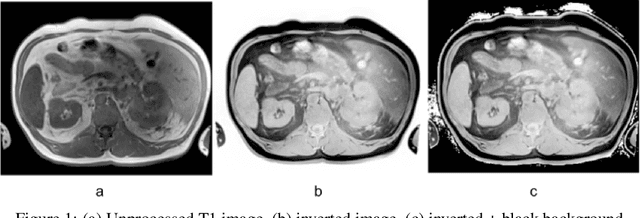

Abstract:Computed tomography (CT) segmentation models frequently include classes that are not currently supported by magnetic resonance imaging (MRI) segmentation models. In this study, we show that a simple image inversion technique can significantly improve the segmentation quality of CT segmentation models on MRI data, by using the TotalSegmentator model, applied to T1-weighted MRI images, as example. Image inversion is straightforward to implement and does not require dedicated graphics processing units (GPUs), thus providing a quick alternative to complex deep modality-transfer models for generating segmentation masks for MRI data.